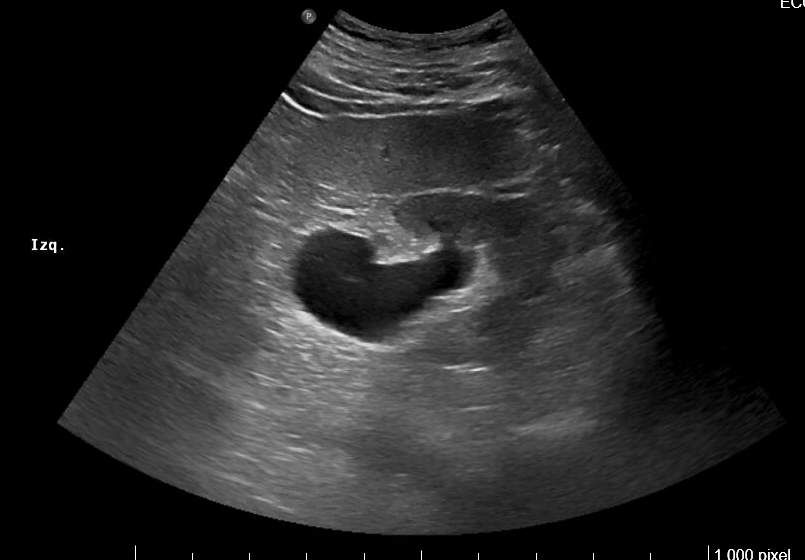

Imágenes 2 y 3. Riñón izquierdo: hidronefrosis grado II. Disminución del grosor cortical. Tamaño 11.5 cm.

Imagen 4. Ecografía de vejiga y próstata: Corte sagital. Vejiga distendida con paredes engrosadas. Crecimiento del lóbulo medio prostático que impronta en vejiga. Volumen aproximado de 127 cc.